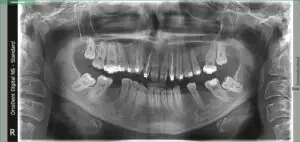

Rendgen snimak nakon lečenja i vađenja zuba

2.Ugradnju implantata – na mestima gde su zubi morali biti izvađeni.